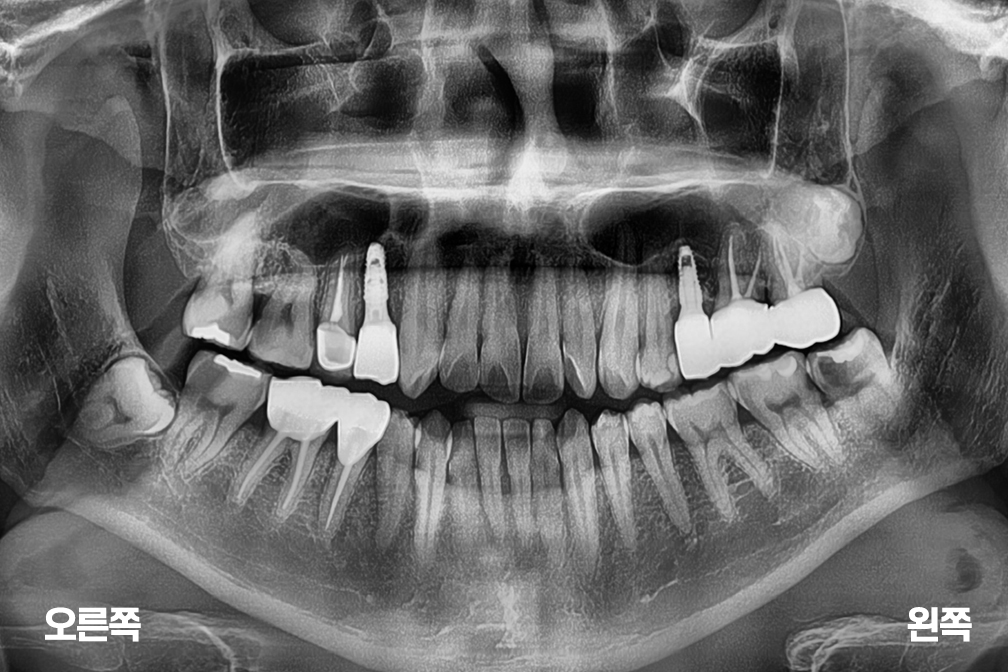

임플란트 수술

Before 2025년 4월 18일